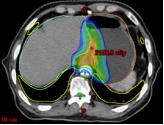

病例展示二:前列腺癌

XXX,男,64岁,主诉:间断性会阴部疼痛10月,确诊为前列腺癌7月。盆腔核磁:前列腺偏左侧异常强化占位,多考虑前列腺Ca,并左侧精囊腺受侵可能,盆腔左侧略大淋巴结。前列腺癌标志物提示:TPSA 88.67 ng/ml,FPSA 3.84 ng/ml。病检:(前列腺穿刺组织左侧)前列腺腺泡腺癌,Gleason评分4+3=7分;(前列腺穿刺组织右侧)Gleason评分3+3=6分。诊断:1、前列腺恶性肿瘤 双侧 腺泡腺癌Gleason评分4+3 =7分 cT3bN0M0 III期 KPS评分:80分。治疗方案:醋酸戈舍瑞林缓释植入剂 10.8mg 皮下注射、比卡鲁胺胶囊 50mg 口服 1次/天”全身治疗,并行前列腺癌碳离子治疗,剂量:57.6 Gy(RBE)/16 Fx。